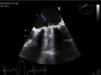

Transesophageal echocardiography performed to clarify the situation revealed mitral prosthetic dysfunction (moderate to severe intraprosthetic pathological regurgitation observed in some cardiac cycles only) due to intermittent interference of the above-described filamentous structure between the prosthetic disks, preventing normal valve function (Figure 1). Fluoroscopy confirmed intermittent incomplete closure of one of the valve disks (Figure 2).